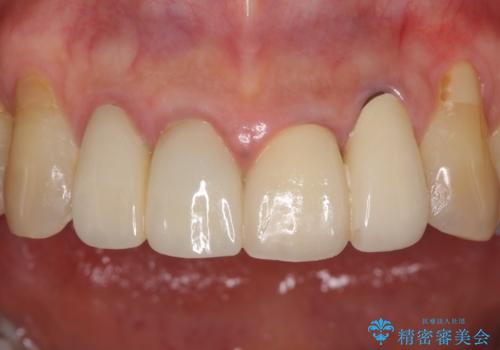

- 昨年治療した前歯の根尖部に痛みを感じ、ラバーダムや顕微鏡を用いた根管治療を希望されて、転院された患者様です。

前医にて神経を取り除いた処置を行った際、ラバーダムが使用されなかったとのことで転院されてきました。

根管治療を実施した後、オールセラミッククラウンに補綴することとしました。

前歯のセラミッククラウンを装着したばかりであったので、根管治療のためにクラウンを壊さなければならないことを残念に思っていらっしゃいました。

しかし、根管治療後はすぐに痛みがひき、治療を受けられて良かったとのことでした。